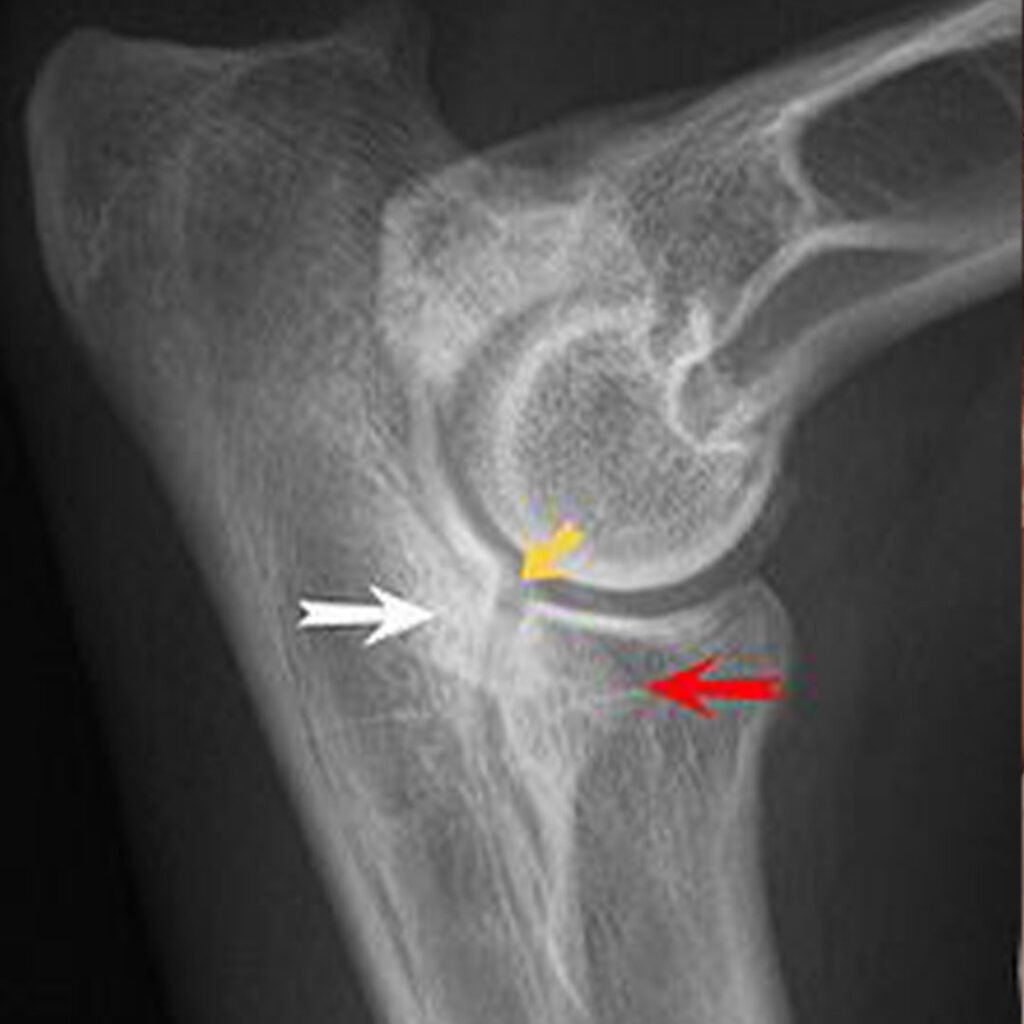

Osteochondrosis dissecans (OCD):

Eine Entwicklungsstörung des Gelenkknorpels, bei der sich Teile des Knorpels lösen und frei im Gelenk bewegen. Dies führt zu einer starken Reibung und Entzündung.

Inkongruenz des Ellenbogengelenks:

Die drei Knochen des Ellenbogengelenks passen nicht richtig zueinander, was zu einer ungleichmäßigen Belastung und zu Schäden im Gelenk führt.

ED – Grad 0: Normal – keine Osteophyten oder Sklerose

ED – Grad I: Milde Arthrose – Osteophyten kleiner als 2 mm oder Sklerose der Gelenkfläche der Elle

ED – Grad II: Moderate Arthrose – Osteophyten zwischen 2 und 5 mm groß

ED – Grad III: Schwere Arthrose – Osteophyten größer als 5 mm